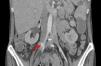

In the postoperative period blood cultures became negative and renal function recovered. Due to pancytopenia, liposomal amphotericin B therapy was switched to intravenous fluconazole. Five days after surgery, the patient suffered acute ischemia of the right lower limb and right iliofemoral embolectomy was performed by vascular surgery. Direct examination of the thrombus revealed C. albicans hyphae. TTE and cardiac magnetic resonance imaging showed no signs of cardiac infection. Thoracoabdominal CT revealed a pseudoaneurysm of the right iliac artery (Figure 3), the probable source of the emboli, and the patient was reoperated, with resection of the aneurysm and replacement by a segment of reversed saphenous vein. Clinical pathological analysis confirmed its infectious etiology and the diagnosis of mycotic aneurysm.